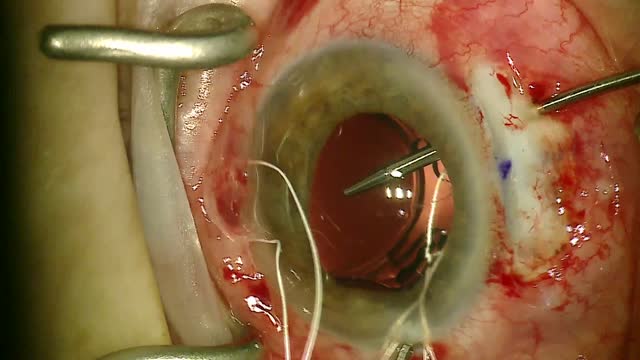

Ahmed Glaucoma Valve (AGV, New World Medical) implantation is an effective treatment for refractory pediatric glaucoma. Studies report success rates as high as 85-90% after 3-4 years, with success often defined as IOP within a specific range (5-21 mmHg) with or without medication. The AGV is attached to a small plate placed under the conjunctiva and is designed with a one-way flow restriction system to prevent hypotony.